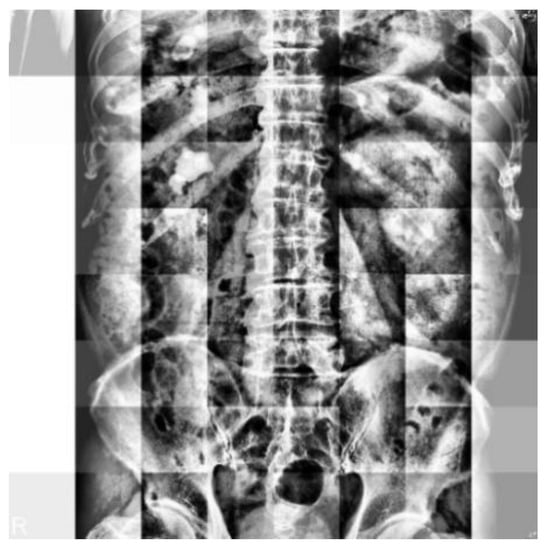

2.2. Datasets

2.3. Image Preprocessing

2.3.2. Image Mask

2.3.3. Image Cropping